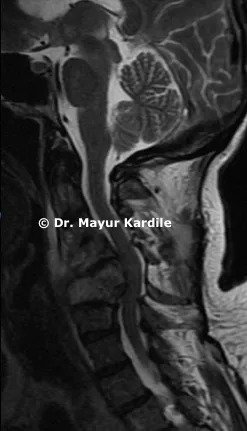

Her MRI revealed infection at C5 and C6 vertebral level with kyphosis

The infective tissue was pressing on the spinal cord giving rise to symptoms of cervical myelopathy

CT scan of the cervical spine revealed complete destruction and collapse of C5 and C6 vertebra with kyphosis deformity